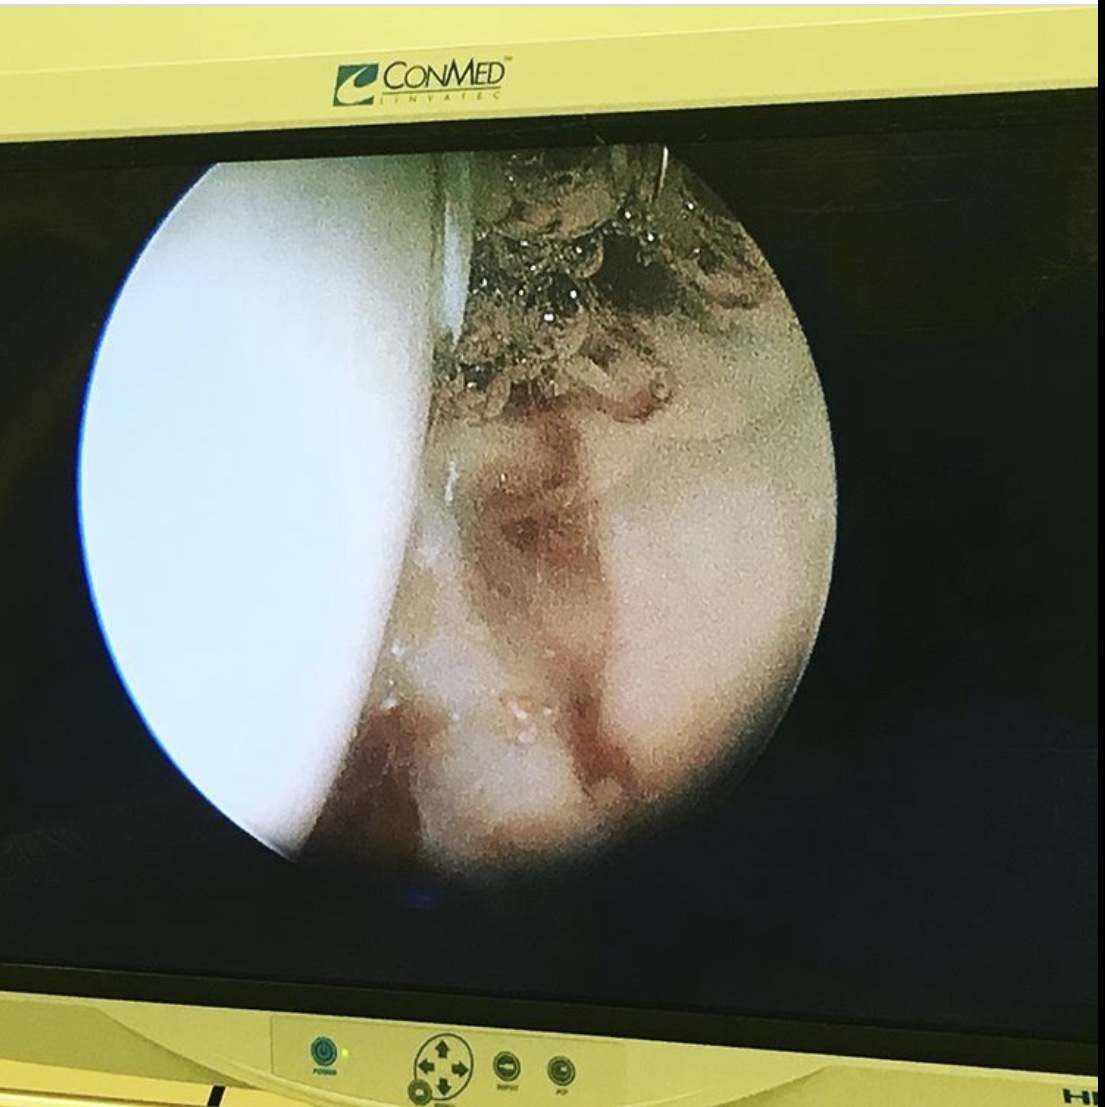

После проведенного МРТ – исследования был установлен диагноз «разрыв губы вертлужной впадины левого тазобедренного сустава».

В ходе операции был проведён релиз суставной губы, резекция остеофитов, шов губы левого тазобедренного сустава.